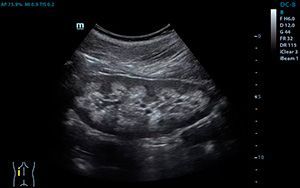

УЗИ почек и надпочечников — неинвазивный диагностический метод, направленный на определение функции органов и желёз, их объёма, строения и расположения. Он даёт хорошие результаты при диагностике ПЧБ, кистозных образований, новообразований добро- и злокачественной природы, а также аномалий развития органов. Что касается надпочечников, то благодаря УЗ-сканированию можно определить этиологию гипертонии, опухоли, причины ожирения и бесплодия.

УЗ-сканирование почек заслуженно считается высокоинформативным и безопасным способом выявления заболеваний органов мочевыделительной системы. Он обеспечивает урологу все необходимые данные для правильной постановки диагноза и назначения соответствующего лечения. Специалисты выделяют два вида ультразвуковых диагностических исследований почек:

• Эхография — направлена на определение состояния почечных структур, выявление их аномалий и опухолей;

• Допплерография — позволяет в режиме реального времени отслеживать кровоток и определить состояние сосудов почек и имеющиеся нарушения.

Узист наносит на исследуемые области медицинский гель, обеспечивающий плотный контакт датчика с кожной поверхностью и исключающий попадание под датчик воздушных пузырьков, затрудняющих визуализацию. Врач водит датчиком по диагностируемой области и поворачивает его под разными углами для того, чтобы добиться качественной визуализации.

Диагностика надпочечников может быть несколько затруднена из-за идентичности структуры их ткани и забрюшинной клетчатки. Это обуславливает ограниченность исследования определением их местонахождения: в случае с правой железой этого удаётся добиться в 90% случаев, с левой — лишь в 50%.

Определение местонахождения осуществляется таким образом: узист определяет правую почку, правую печёночную долю, нижнюю полую вену и вычисляет железу в области, создаваемой крайними точками вышеперечисленных анатомических структур.